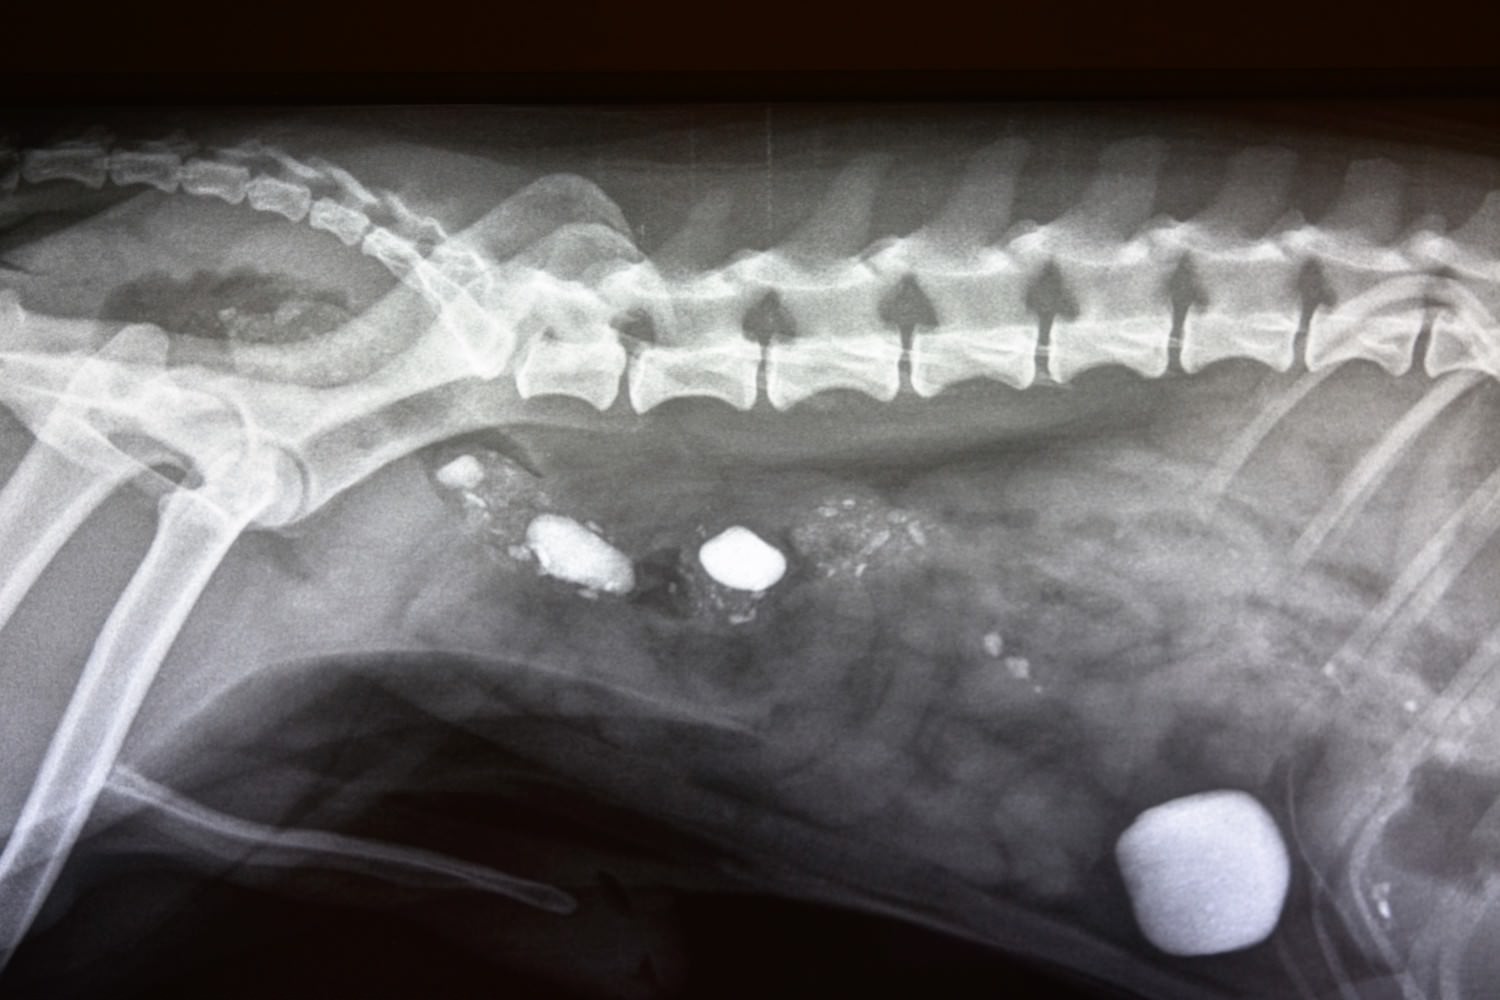

Røntgen

Røntgen er et godt diagnostisk hjelpemiddel for å undersøke beinvev og bløtdeler, og vårt digitale røntgenutstyr gir topp billedkvalitet.